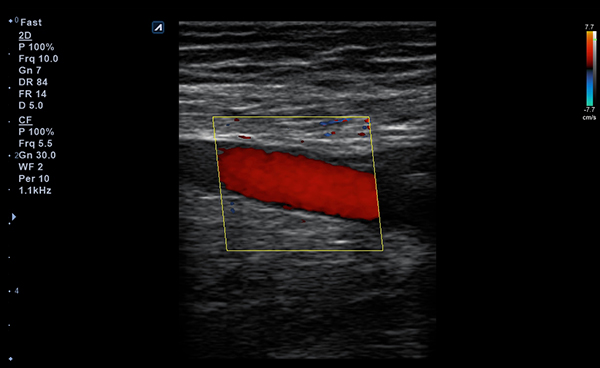

Con Convex y Linear, dos tipos de transductores, puede escanear tanto las

partes más superficiales como las más profundas del cuerpo humano.

Los transductores tienen un amplio rango de aplicaciones y pueden ser utilizados en

una gran variedad de situaciones clínicas.

- Imaging modesB-mode, CF, M, PW, PD

- Frequency3-12 MHz